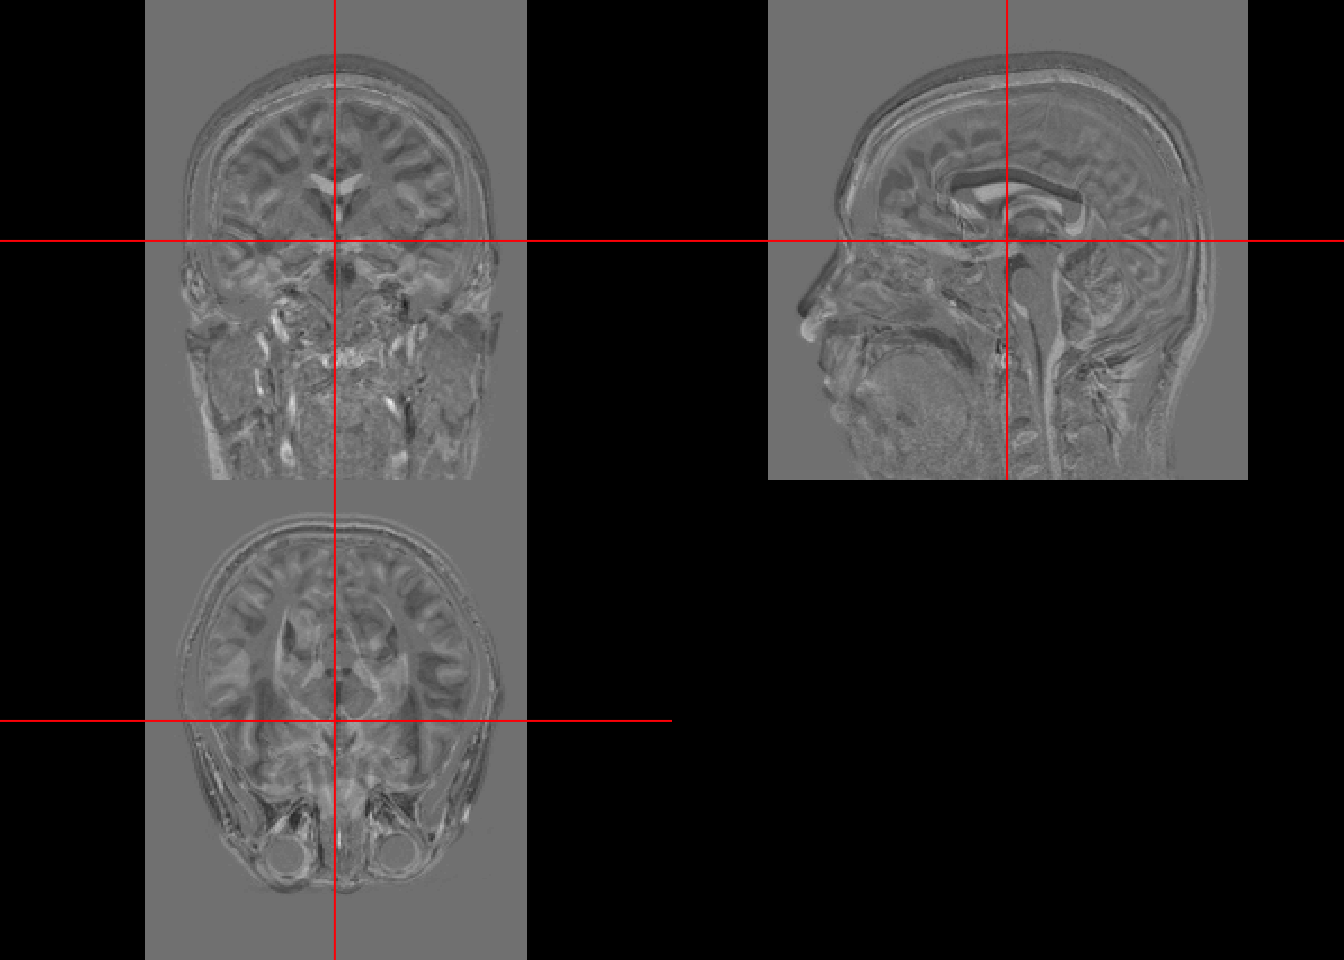

This lecture covers: - Masking - Operations

mask = readNIfTI(maskfpath, reorient=FALSE) 4.2 Visualization

This brain was collected with a bigger FOV than the previous scans. Thus a lot of body parts other than brain are shown.